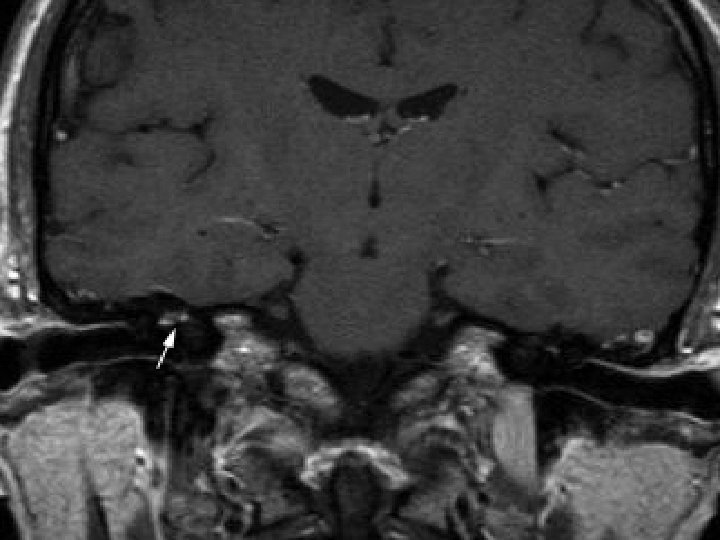

(4) Neurologist assessment: summary Initial presenting illness n Bulbar palsy with normal NCT, but clinically nil response to IVIG and steroid Deterioration right now n Cerebral dysfunction with raised CSF protein n Hypointensities in bilateral temporal and Rt BG Need to consider other diagnosis n Sinusitis with orbital + CNS extension n For contrast MRI brain + skull base

Searching for an answer, again…. . n n n n n 9 th July: Plain CT Brain (Hospital A) 7 th Aug: Plain CT Brain (Hospital A) 25 th August: Plain CT Orbit (Hospital A) 27 th August: Contrast CT brain + Sinus 4 th September: MRI brain + brainstem 4 th September: Plain CT brain 10 th September: Contrast CT brain 11 th September: Plain CT sinus 15 th September: MRI brain + DWI

Brain was so ill, but no answer…. Condition since 4 th September 2010 n Multi-focal inflammatory change over bilateral basal ganglia/ thalamus/ temporal lobes and brainstem on MRI, unlikely due to bacterial infection n GCS E 4 Vt. M 1 and all limbs flaccid n Persistent high fever and tachycardia despite Vanco/netro/fluconazole 14 days

Summary of progression • June/ 2010 n • July/ 2010 n • Early Aug/ 2010 n • Late Aug/ 2010 n • Sept/ 2010 n Lt face weak Bulbar palsy Dilated Rt pupil and uveitis Endophthalmitis and high fever Deep coma, tetraplegia, high fever n n n Nil imaging Facial neuritis Bilateral basal ganglia change Bilateral temporal + BG + thalami + pons